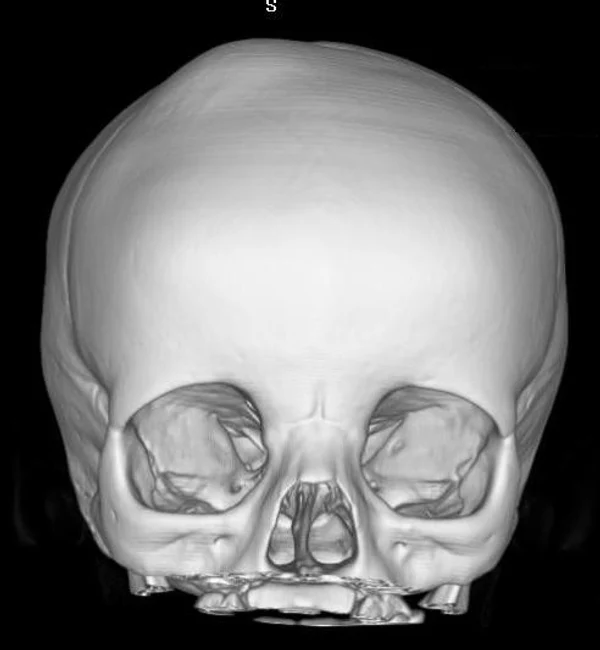

Удаление опухолей черепаВ качестве примера лечения пациентов с опухолями черепа привожу личное наблюдение пациента грудного возраста с опухолью черепа. В возрасте 1 мес. у ребёнка в затылочной области слева родителями обнаружено плотное образование диаметром 5 мм. За 3 мес. до госпитализации образование значительно увеличилось в размерах. При поступлении в возрасте 6 мес. в затылочной области слева (в проекции лямбдовидного шва) имеется безболезненное, плотное, неподвижное, бугристое образование размерами 5 х 4 х 2 см. При КТ и МРТ головы выявлена опухоль черепа в области астериона слева, обладающая преимущественно интракраниальным ростом (рис. 30 а). Ребёнку выполнено удаление опухоли черепа (рис. 30 б). Образовавшийся дефект черепа больших размеров закрыт перфорированной титановой пластиной (рис. 30 в). При наблюдении пациента в течении 2-х лет рецидива заболевания и деформации черепа не отмечалось.